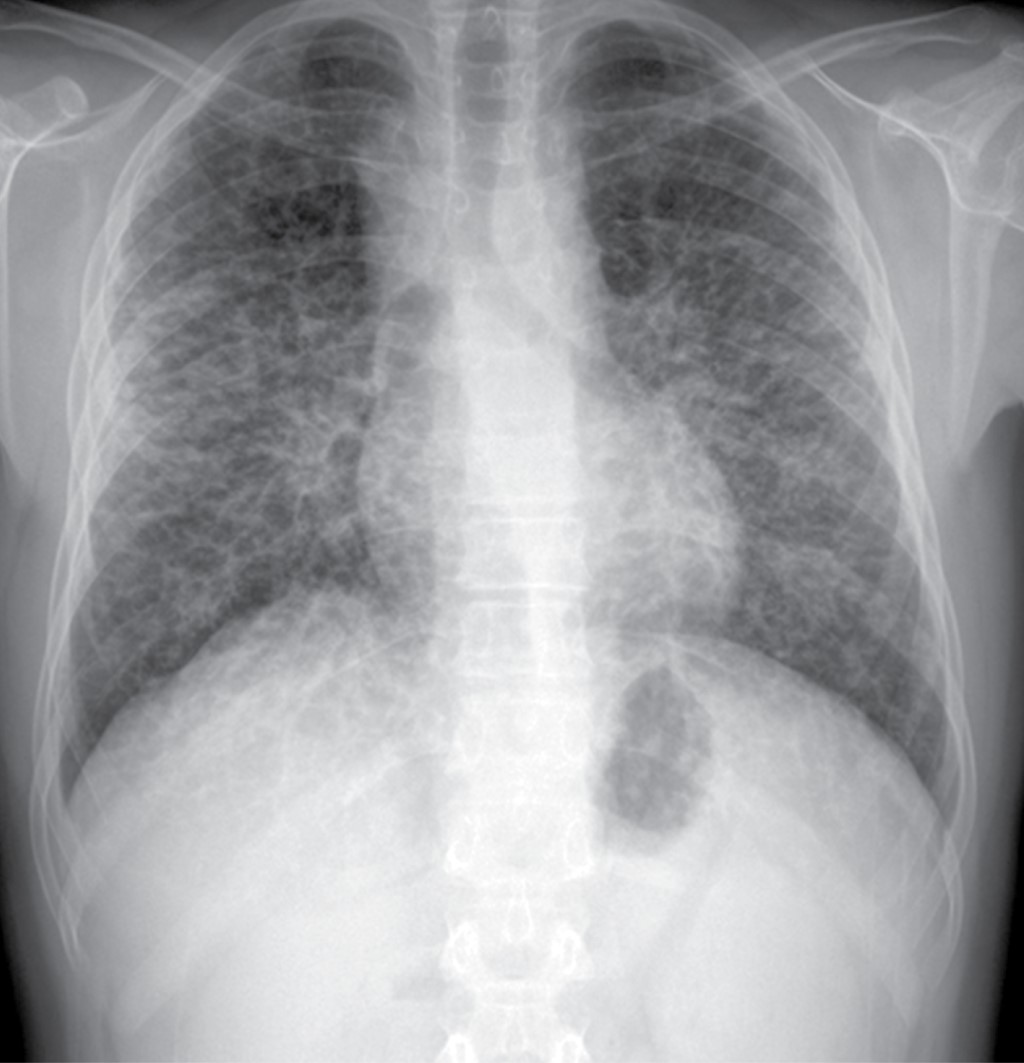

La radiografía de tórax inicial mostró: ensanchamiento parahiliar bilateral por crecimientos ganglionares y un patrón intersticial fino bilateral y difuso, casi simétrico con algunas imágenes micronodulares bilaterales (Figura 1).

La radiografía de tórax mostró ensanchamiento mediastinal y un patrón intersticial grueso a expensas de intersticio perilobulillar bilateral y difuso, casi simétrico con algunas imágenes nodulares también difusas (Figura 9). En la TACAR contrastada se corrobora el patrón intersticial perilobulillar con nódulos difusos con discreto predominio subpleural así como zonas de atelectasia bilateral subpleurales y en lóbulo medio (Figura 10). En la ventana mediastinal se demuestran crecimientos ganglionares paratraqueales de predominio derecho, en ventana aortopulmonar y axilar bilateral. A nivel abdominal lesiones nodulares hipodensas múltiples hepatoesplénicas sugestivas de granulomas (Figura 11). Se realizó biopsia de piel en cara, la cual mostró dermatitis granulomatosa epitelioide no caseificante, compatible con sarcoidosis (Figura 12).

La radiografía de tórax es anormal en 90% de los casos. Los dos hallazgos más característicos son la linfadenopatía mediastinal bilateral acompañada de enfermedad intersticial nodular del pulmón, éstos sirven para la estadificación de la enfermedad,5,8 siendo la TACAR la herramienta más valiosa para el diagnóstico (Tabla 1).

Las adenopatías paratraqueales bilaterales e hiliares son las más comunes. Los patrones radiológicos parenquimatosos más comunes son las opacidades reticulonodulares (90%) en las zonas superiores del pulmón, afección alveolar y fibrosis pulmonar. El patrón miliar es raro a cualquier edad.1,5,8

Nuestros casos se clasifican en el estadio II, ya que en la TACAR se detectó adenopatía hiliar bilateral con infiltrados pulmonares (Tabla 1).